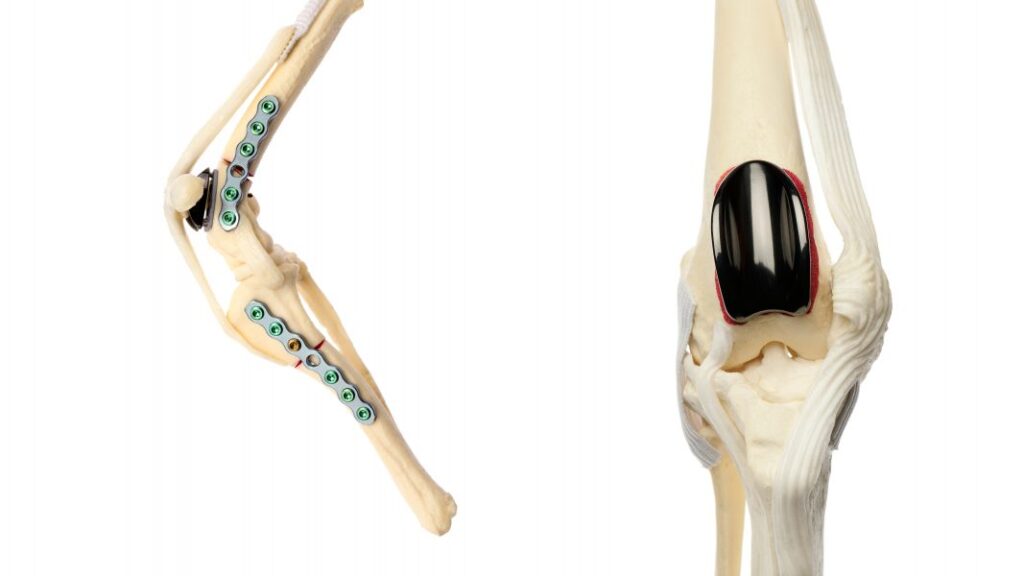

PGR (Patellar Groove Replacement)

Aşırı derecede hasar almış Patellar Oluk durumlarında bu oluğun bir protezle değiştirilmesi gerekir. Bu amaçla yüksek teknoloji ile üretilmiş doku uyumlu protezler kullanılır. Türkiye’nin ilk PGR operasyonu merkezimizde yapılmıştır. Şu anda da gerekli vakalarda başarı ile uygulanmaya devam edilmektedir.